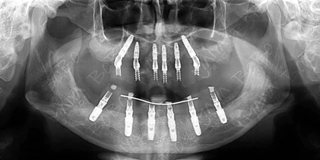

种植方案:ALL-ON-6即刻负重种植

手术CT片